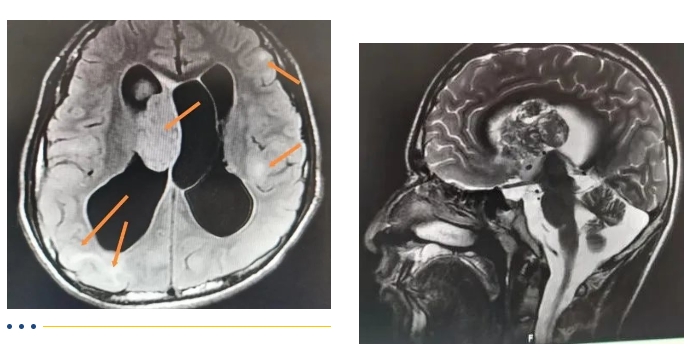

全国知名小儿脑科专家来到市第五医院,不仅面对面义诊,还用顶尖技术为患儿成功进行手术